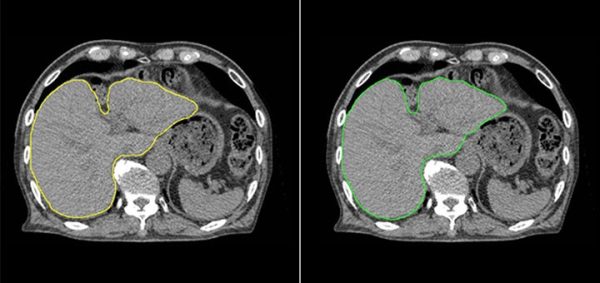

肝臓モデルを使用した例では、輪郭作成に要する時間は、従来の手作業のみでは30分以上要したものが、臨床利用ための人による修正時間も含め、Ai-Segによる自動輪郭作成及び必要に応じての軽微な修正作業を合わせて5分程度までに短縮することができた。図1に示すように医師とAi-Segが作成した輪郭を比較しても違いがわからないほどの水準にまで達している。